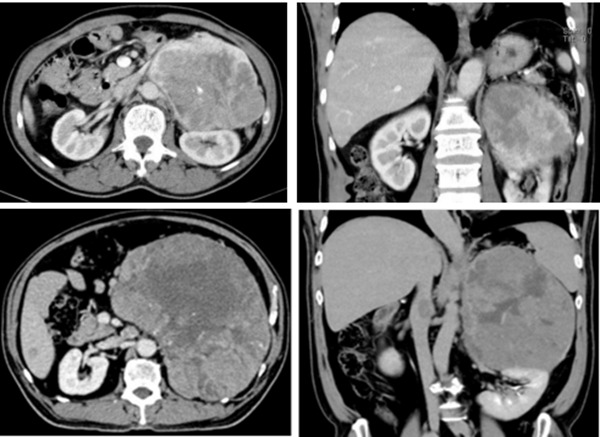

据悉,该院收治的两名巨大肾上腺皮质癌患者中,一名68岁男性因左腹疼痛1周入院,检查显示患者左侧肾上腺约18×15cm巨大肿瘤侵犯肾门血管,手术难度极高;另一名56岁男性因发现腹膜后肿物半年入院,检查显示左肾上腺25×18cm巨大肿瘤同时累及左肾,并伴左肾静脉及下腔静脉癌栓形成,手术切除风险极大。

针对患者病情,李源教授团队联合血管外科、胆胰外科、麻醉科、代谢与内分泌科、重症医学科及肿瘤科等多学科专家进行会诊,制定了个性化手术方案。术中,团队精细操作,成功为第一例患者完整切除肿瘤及肾静脉并行左肾静脉重建术;为第二例患者实施左肾上腺巨大肿瘤切除术+左肾静脉癌栓取出术,耗时约4小时后完整切除肿瘤及癌栓,并成功为患者保留了左侧肾脏及其功能。两例患者术后均恢复顺利,后续计划至肿瘤科行下一步治疗。